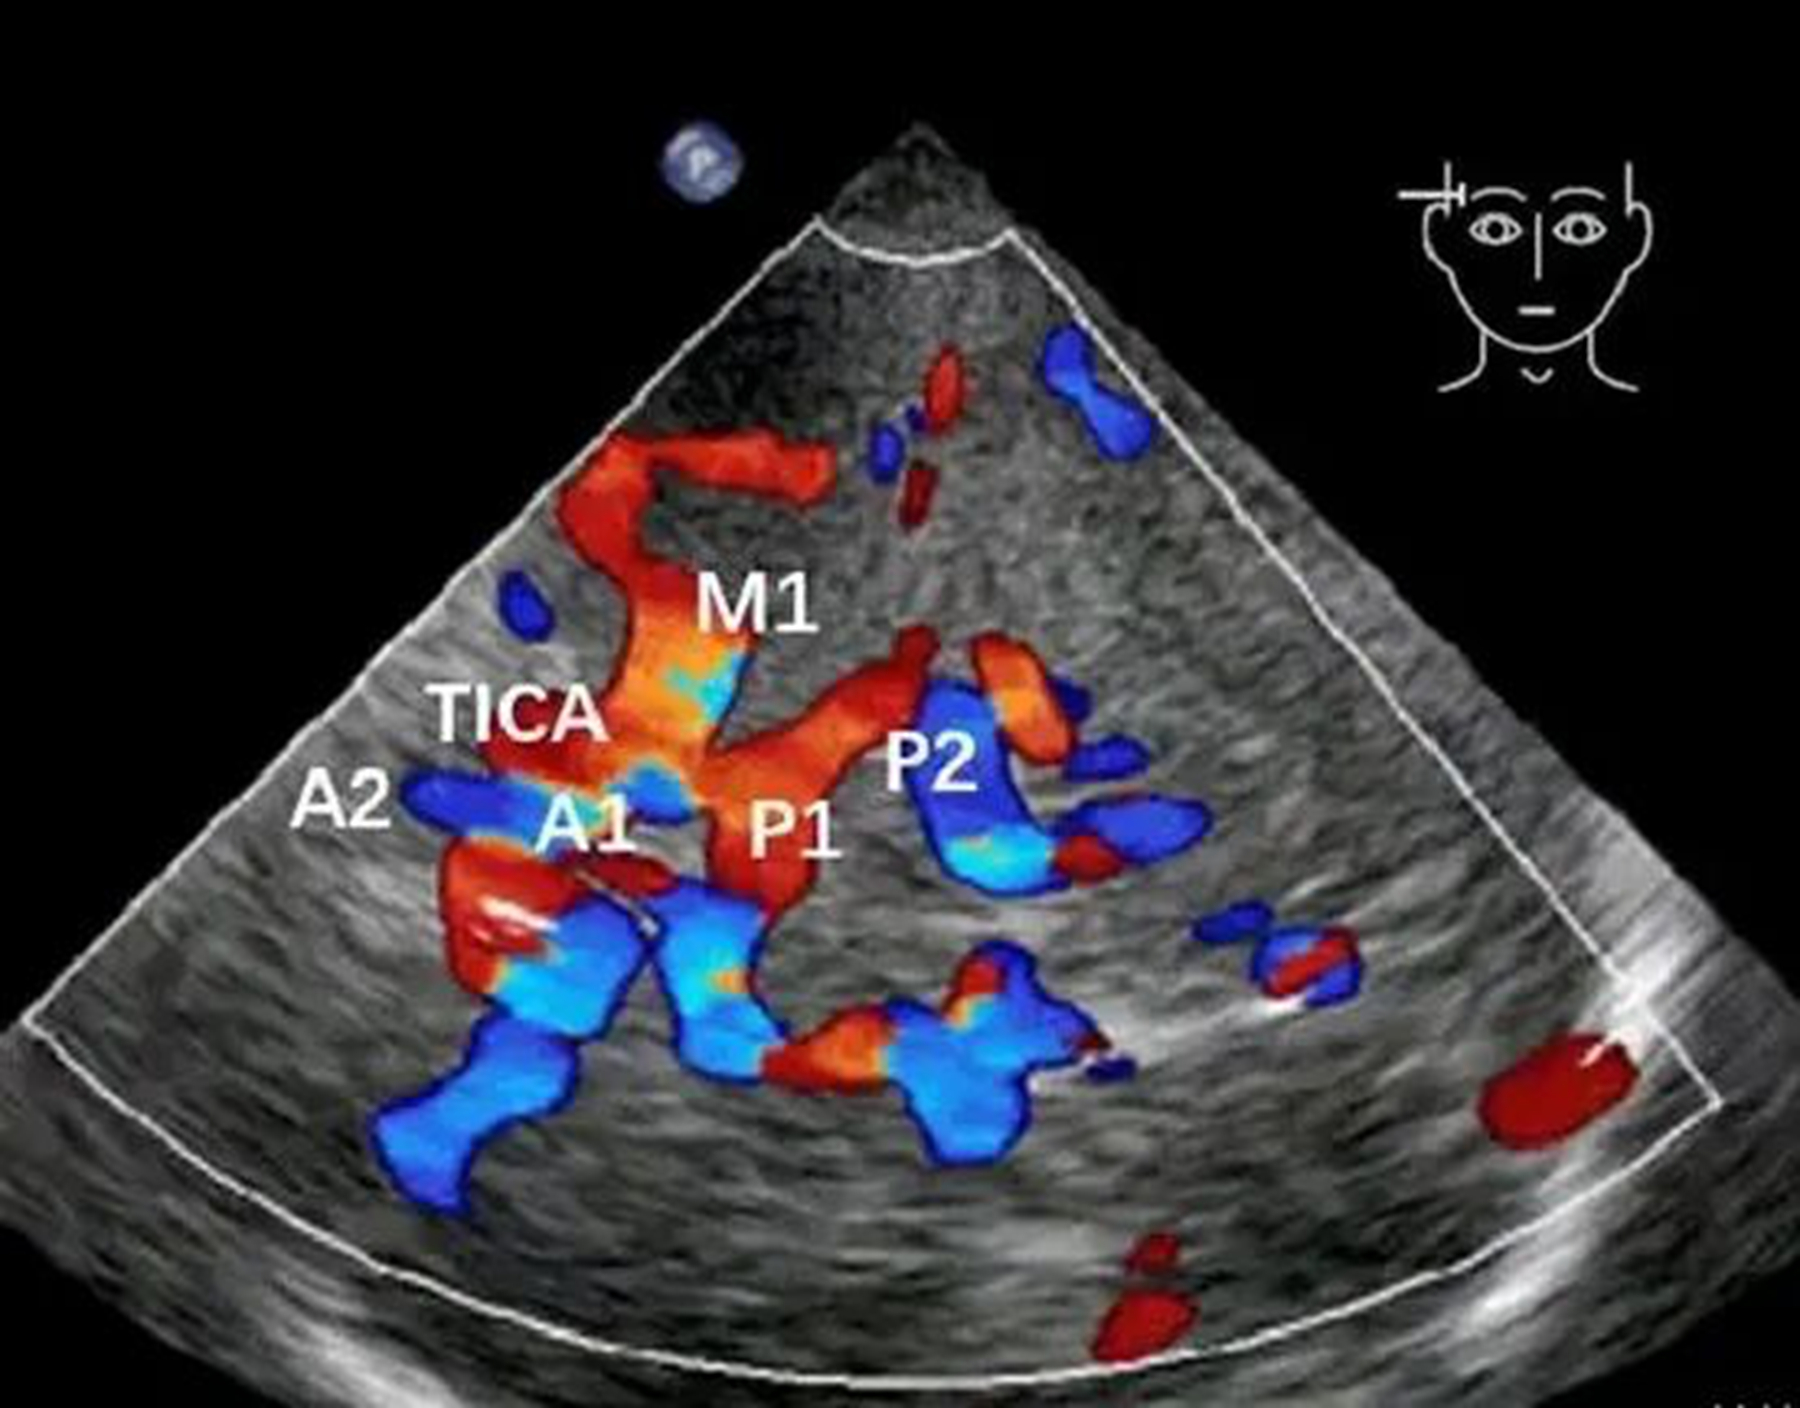

简单来说,TCCD 相当于专门为颅内血管打造的彩色 B 超。依托颅骨天然薄弱的透声窗,超声探头可穿透颅骨屏障,在显示屏上实时、动态呈现颅内各大动脉的清晰血流影像。

医生能够直观观察血管走形是否迂曲、血流速度有无异常增快、是否存在异常涡流等问题,让脑血管检查从 “只靠听” 变成 “看得见、看得清”。